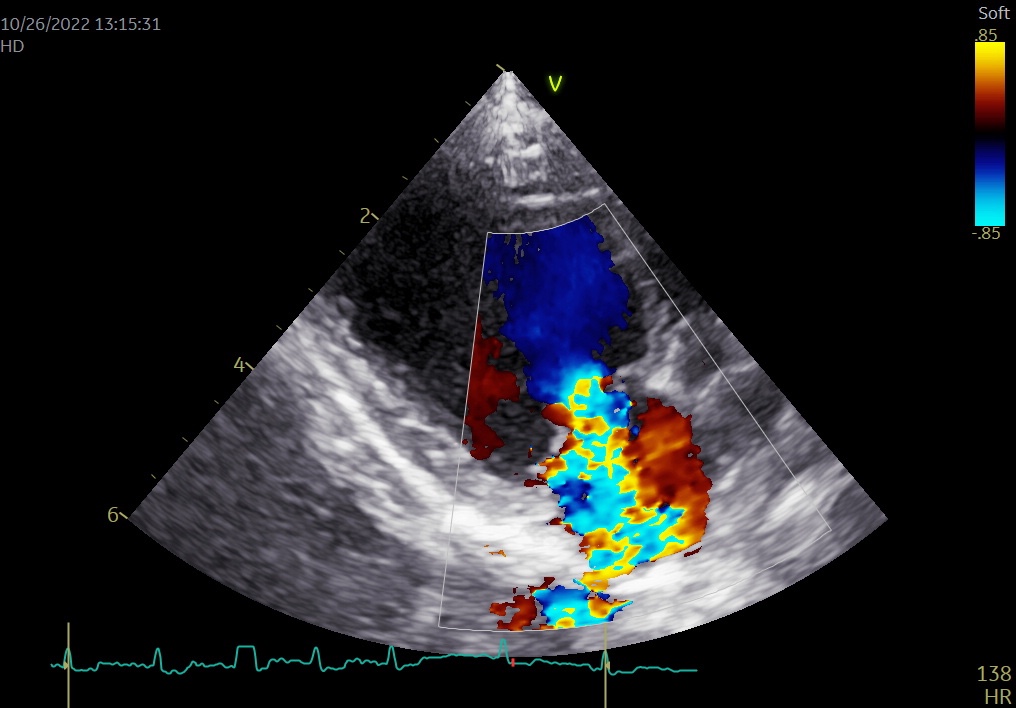

僧帽弁閉鎖不全症は、犬種特異性、特徴的な心雑音、胸部レントゲン検査などにより比較的容易に診断が可能ですが、心エコー図検査による逆流血流の検出、およびその程度や病態の把握、合併症などを明らかにすることで、確定診断と病態評価に基づいた治療を実施できるようになります。

- 僧帽弁の粘液腫様変性

- カラードプラによる僧帽弁逆流の確認